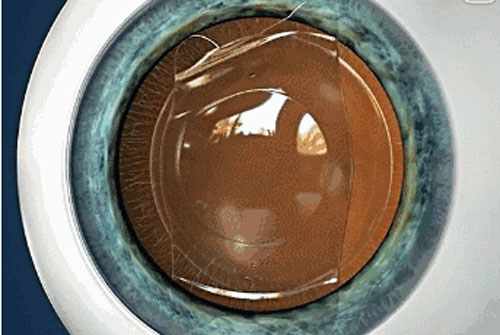

ICL晶体植入手术无需切削角膜组织,而是将小小的“眼镜”植入眼内,具有可逆性,适合近视1800度以内、散光600度以内的高度近视者,还可一次性解决散光、远视、老花等问题。